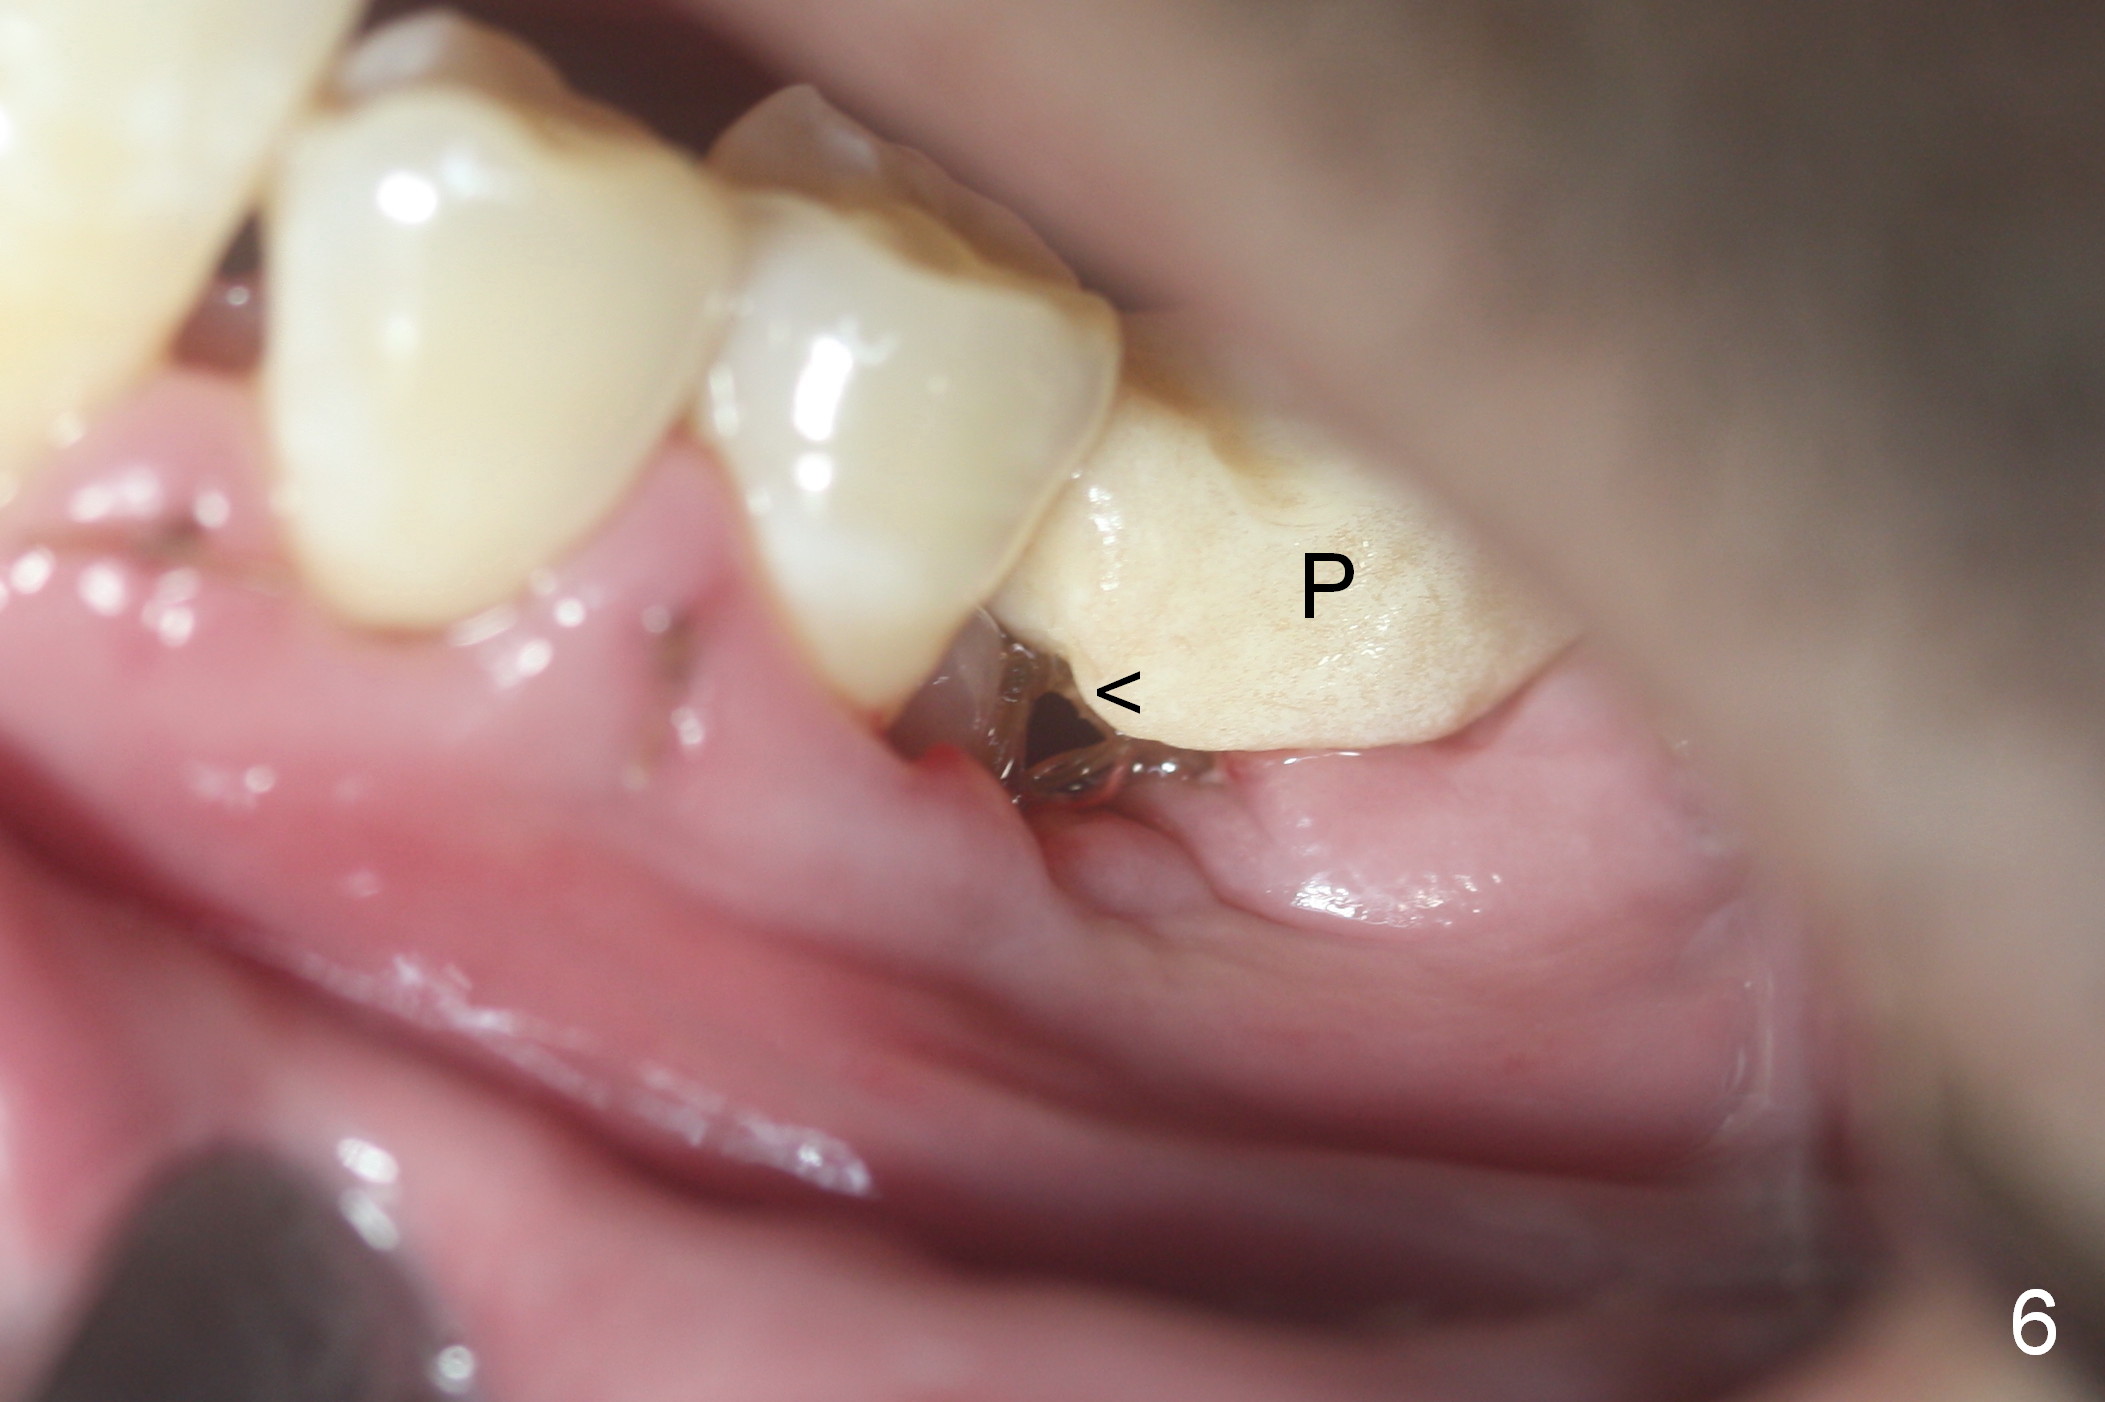

The patient is doing well postop.  The mesial socket appears to have collapsed 7 days postop (Fig.6 <).  The mesial portion of the immediate provisional (P) should have been overbuilt to compensate for the socket with lost buccal and lingual plates.